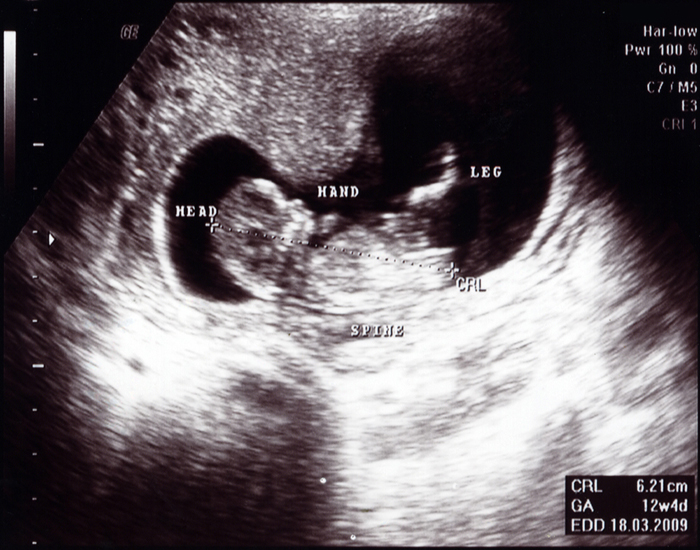

Çavdar, yulaf, arpa ve bakliyatlarla zenginleştirilmiş olan yiyeceklerle beslenmek, bağırsak sorunları yaşanmasını ve bebeğin rahatsız olmasını önler. 13 haftalık bebek diğer haftalara göre biraz daha büyümüştür; Hafta gebelik haftasında bebeğiniz şimdi baştan popoya 6,8 cm ile 8,0 cm arasında ve yaklaşık 14,2 g ila 21,3 g ağırlığındadır. Haftada bebeğinizin kol ve bacaklarındaki kemikleri oluşmaya ve bağırsakları göbek kordonundan karına doğru yayılmaya başlar. Ancak kalbin küçük olması nedeniyle bebeğin kalp atışları anne tarafından hissedilemez. Hamileliğinizin 13.haftası ile birlikte ikinci trimester dönemine girmiş bulunmaktasınız. Haftası, tıpkı annede olduğu gibi bebekte de birçok gelişmeyi beraberinde getirir. 13 haftalık bir bebek, anne karnında yaklaşık 6,5 ila 7,8 cm büyüklüğünde ve 13 ila 20 gram ağırlığındadır. Hafta bebek gelişimi ve anne karnında bebek gelişimi bilgileri hürriyet aile�de!

Ancak kalbin küçük olması nedeniyle bebeğin kalp atışları anne tarafından hissedilemez. 13 aylık bebek fiziksel gelişimi. Bebeğin gözleri daha önce birbirinden uzakken bu haftada birbirine yaklaşmaya başlar, kulaklar normal yerlerine doğru ilerler ve bebeğin yüzü normal insan yüzüne benzemeye başlar. 13 haftalık gebelik döneminde artık bebeğiniz bir şeftali boyutuna gelmiş durumdadır. 13 haftalık bebek olarak büyüklüğü ise neredeyse bir limon boyutuna ulaştı diyebiliriz. Bebek gelişimi ve vücutta değişiklikler.

Beyin gelişimi hızla devam eder ve baş büyüklüğü gövdenin birkaç katıdır. 13 haftalık bebeğin boyu kaç cm olmalıdır? Çoğu kadın bu üç ayda enerji patlaması bile hisseder. 13 haftalık bebek gelişimi nasıl olur? Bebeğin de bir şeftali boyutuna ulaştı. 13 haftalık bebeğin kalp atışı hissedilir mi?

13 haftalık bir bebek, anne karnında yaklaşık 6,5 ila 7,8 cm büyüklüğünde ve 13 ila 20 gram ağırlığındadır. Hafta gebelik haftasında bebeğiniz şimdi baştan popoya 6,8 cm ile 8,0 cm arasında ve yaklaşık 14,2 g ila 21,3 g ağırlığındadır. 13 haftalik gebeli̇k (hami̇leli̇k) görüntüsü.

13 haftalık bebeğin kalp atışı hissedilir mi? Anne karnında 13 haftalık bebek yaklaşık 6.5 ila 7.8 cm büyüklüğünde ve13 ile 20 gr ağırlığındadır. Trimesterının başındasınız ve 4 aylık hamilesiniz.

Hafta itibari ile anne adayındaki değişim ve gelişim bebeğinizin gelişimi devam ettikçe sizin de rahminiz büyümeye, bunun etkisiyle de gerilmeye başlar. Beyin gelişimi hızla devam eder ve baş büyüklüğü gövdenin birkaç katıdır. Hafta gebelik haftasında bebeğiniz şimdi baştan popoya 6,8 cm ile 8,0 cm arasında ve yaklaşık 14,2 g ila 21,3 g ağırlığındadır.

İkinci üç aya hoş geldiniz! Gebelik haftasında bebeğin boyu yaklaşık olarak 7 cm, ağırlığı 25 gram kadardır. Trimesterının başındasınız ve 4 aylık hamilesiniz.

Hamilelik üç dönemden oluşur, 13 haftalık gebelik sürecinin bitmesiyle birlikte ilk dönem sona erer. 13 haftalik gebeli̇k (hami̇leli̇k) görüntüsü. Gebeliğin ilk trimester dönemi hamileliğin 1.haftası ila 12.haftası arası sürer.

13 haftalık bebeğin boyu kaç cm olmalıdır? Bebeğin gözleri daha önce birbirinden uzakken bu haftada birbirine yaklaşmaya başlar, kulaklar normal yerlerine doğru ilerler ve bebeğin yüzü normal insan yüzüne benzemeye başlar. Haftada bebeğinizin kol ve bacaklarındaki kemikleri oluşmaya ve bağırsakları göbek kordonundan karına doğru yayılmaya başlar.